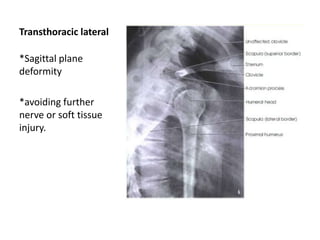

Transthoracic lateral

*Sagittal plane

deformity

*avoiding further

nerve or soft tissue

injury.